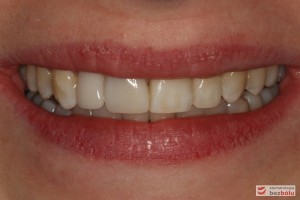

Pacjentka lat 26 zgłosiła się do gabinetu celem korekcji uśmiechu. Głównym zmartwieniem były problemy estetyczne, które znacznie wpływały na jakość życia pacjentki. Wykonano leczenie zachowawcze zębów oraz analizę cefalometryczną i analizę modeli diagnostycznych. Zaplanowano leczenie aktywne aparatem DAMON dla szczęki i żuchwy, które trwało 2 lata. Po fazie leczenia aktywnego rozpoczęto leczenie retencyjne z użyciem szyny tłoczonej dla szczęki i retainera stałego dla żuchwy.